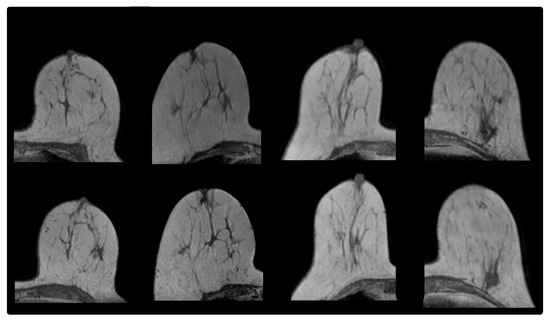

2.1.1. Prone-Prone